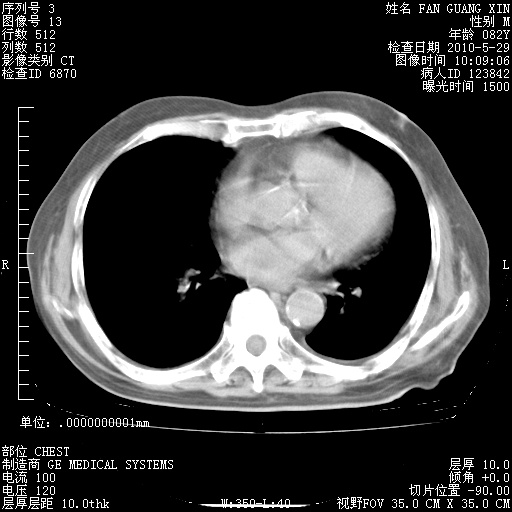

治疗3周后的肺部CT纵隔窗

再治疗10天后的肺部CT